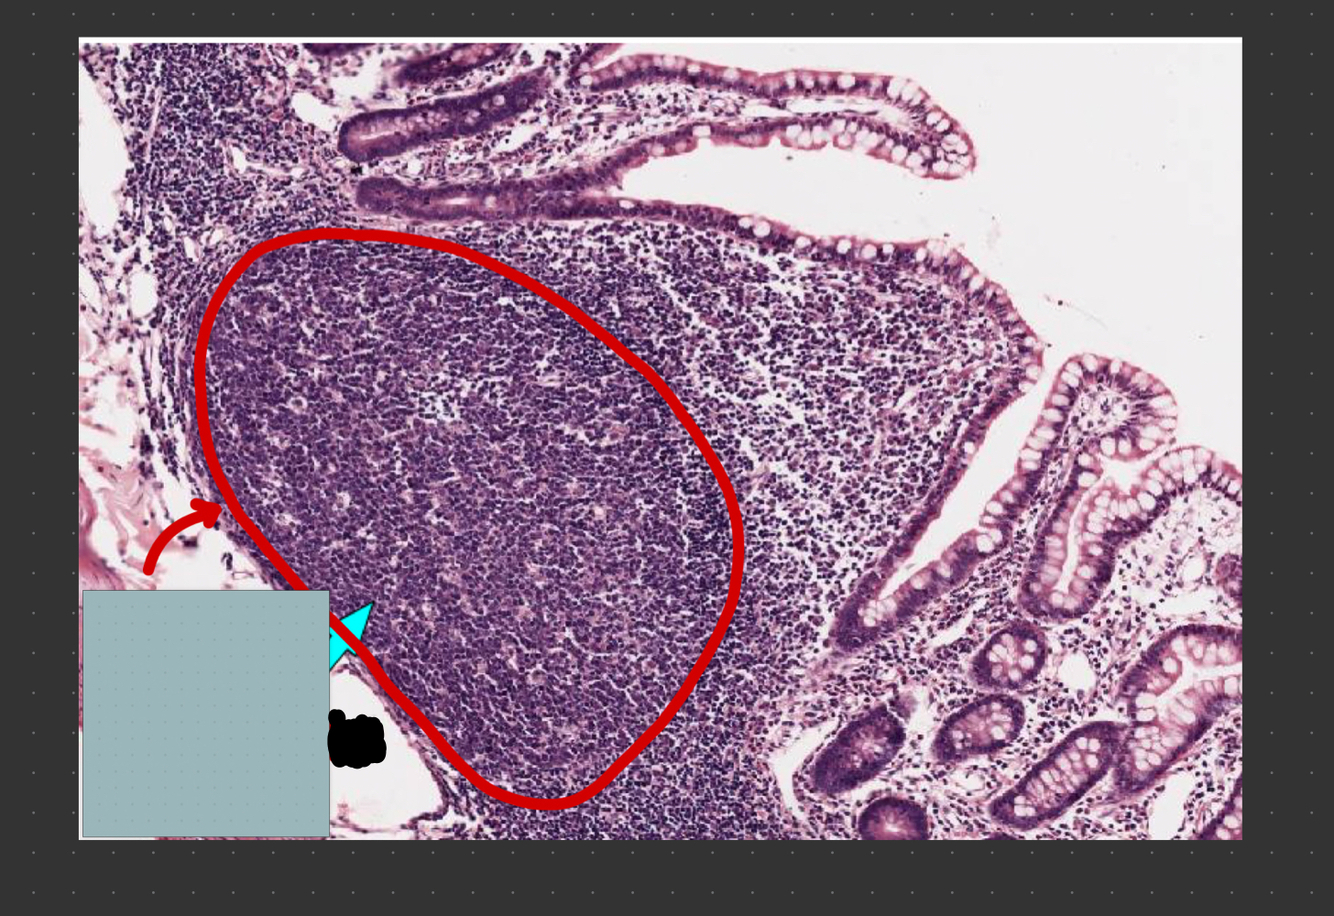

What structure is circled in red?

active 2° lymphoid nodule with germinal center